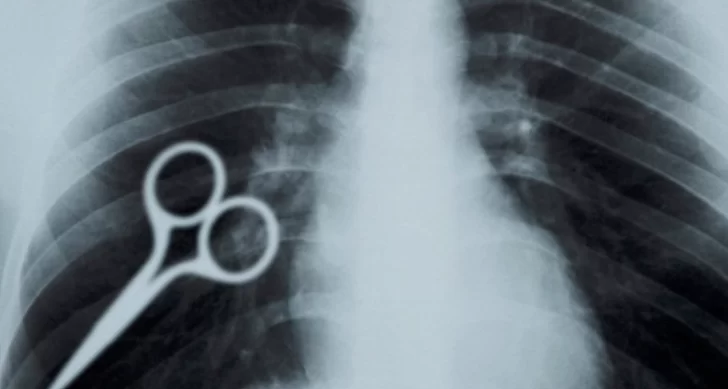

Axel Hernán Rojas está alojado en el Servicio Penitenciario Provincial cumpliendo una pena por delitos contra la propiedad desde finales de 2019 y en las últimas horas fue noticia luego de tragarse una tijera en lo que, se supone, es un acto de protesta.

La acción del reo obligó a que los penitenciarios resolvieran su traslado a un hospital -previa autorización del Juzgado de Ejecución Penal- para que le realicen las actuaciones de rigor a fin de sacarle el elemento de su cuerpo.

Por el tamaño del objeto, el hombre terminó expulsándolo por sus propios medios.